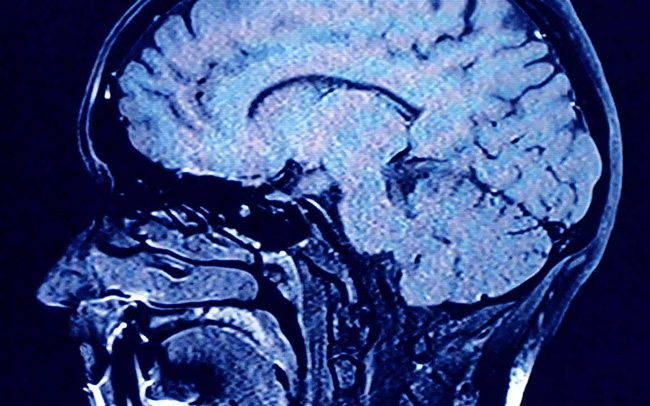

Disciplina u okviru psihijatrije koja se bavi proučavanjem neurološke osnove različitih psihičkih oboljenja, ali i poremećaja ponašanja naziva se neuropsihijatrija.

Generalno, neuropsihijatrija je podeljena na neurologiju i psihijatriju.